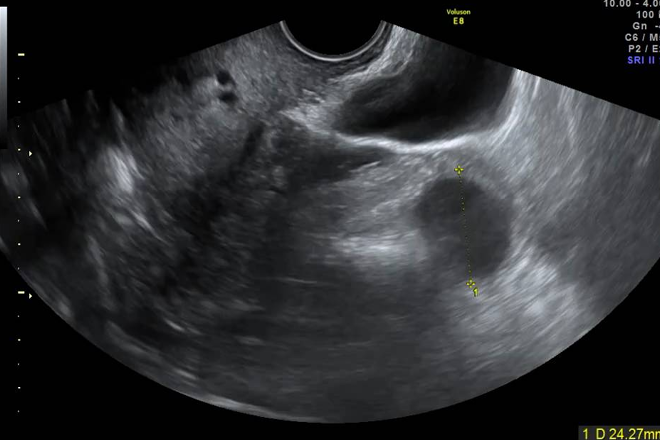

Mujer de 48 años en excelente estado general, presenta dolor abdominal bajo en mayo de 2002. Durante el examen ginecológico y ecografía se observa un anexo derecho de localización posterior con ovario aumentado de tamaño, sólido quístico. Los niveles de Ca 125 están elevados (1587 U/ml). La tomografía revela múltiples nódulos pulmonares bilaterales sugestivos de metástasis. En la laparotomía se identifican focos de endometriosis quística en el ovario y peritoneo pélvico, los cuales se resecan y confirman por biopsia. Se destaca la histerectomía total y salpingoooforectomía izquierda previas. La biopsia uterina muestra múltiples nódulos miomatosos sin características malignas. No se encuentran lesiones en el ovario ni la trompa.

Los leiomiomas del cuello uterino de gran tamaño son poco comunes. En la exploración ginecológica, se evidencia una miomatosis de grandes dimensiones, con una masa móvil en el fondo uterino que en realidad corresponde al cuerpo uterino de tamaño prácticamente normal. La discrepancia entre los hallazgos clínicos y las imágenes destaca la importancia de una evaluación detallada para un diagnóstico preciso.